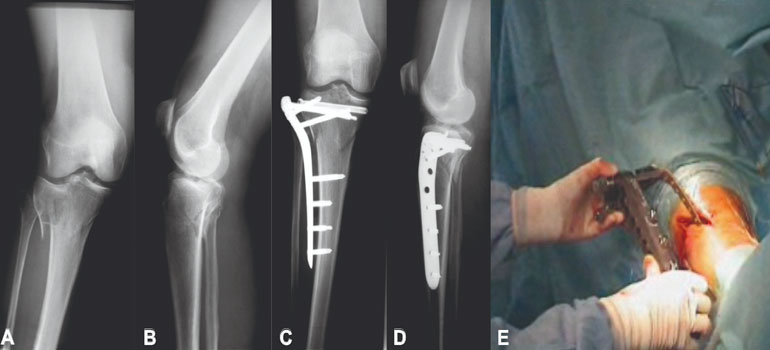

Minimally invasive orthopaedic surgery includes joint replacements and arthroscopies (hip, knee, ankle, wrist, shoulder and elbow and knee osteotomy (realignment).